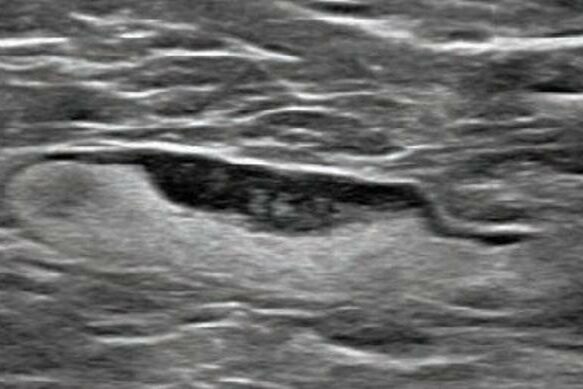

Παρουσιάζουμε ἰδία περίπτωση χρήσεως μεμβράνης κατασκευασμένης ἀπό PRF (πλάσμα αἵματος πλούσιο σέ αἱμοπετάλια) γιά τήν κάλυψη ἱστικοῦ ἐλλείμματος πάχους 4 – 5 χιλιοστῶν, τό ὁποῖο…